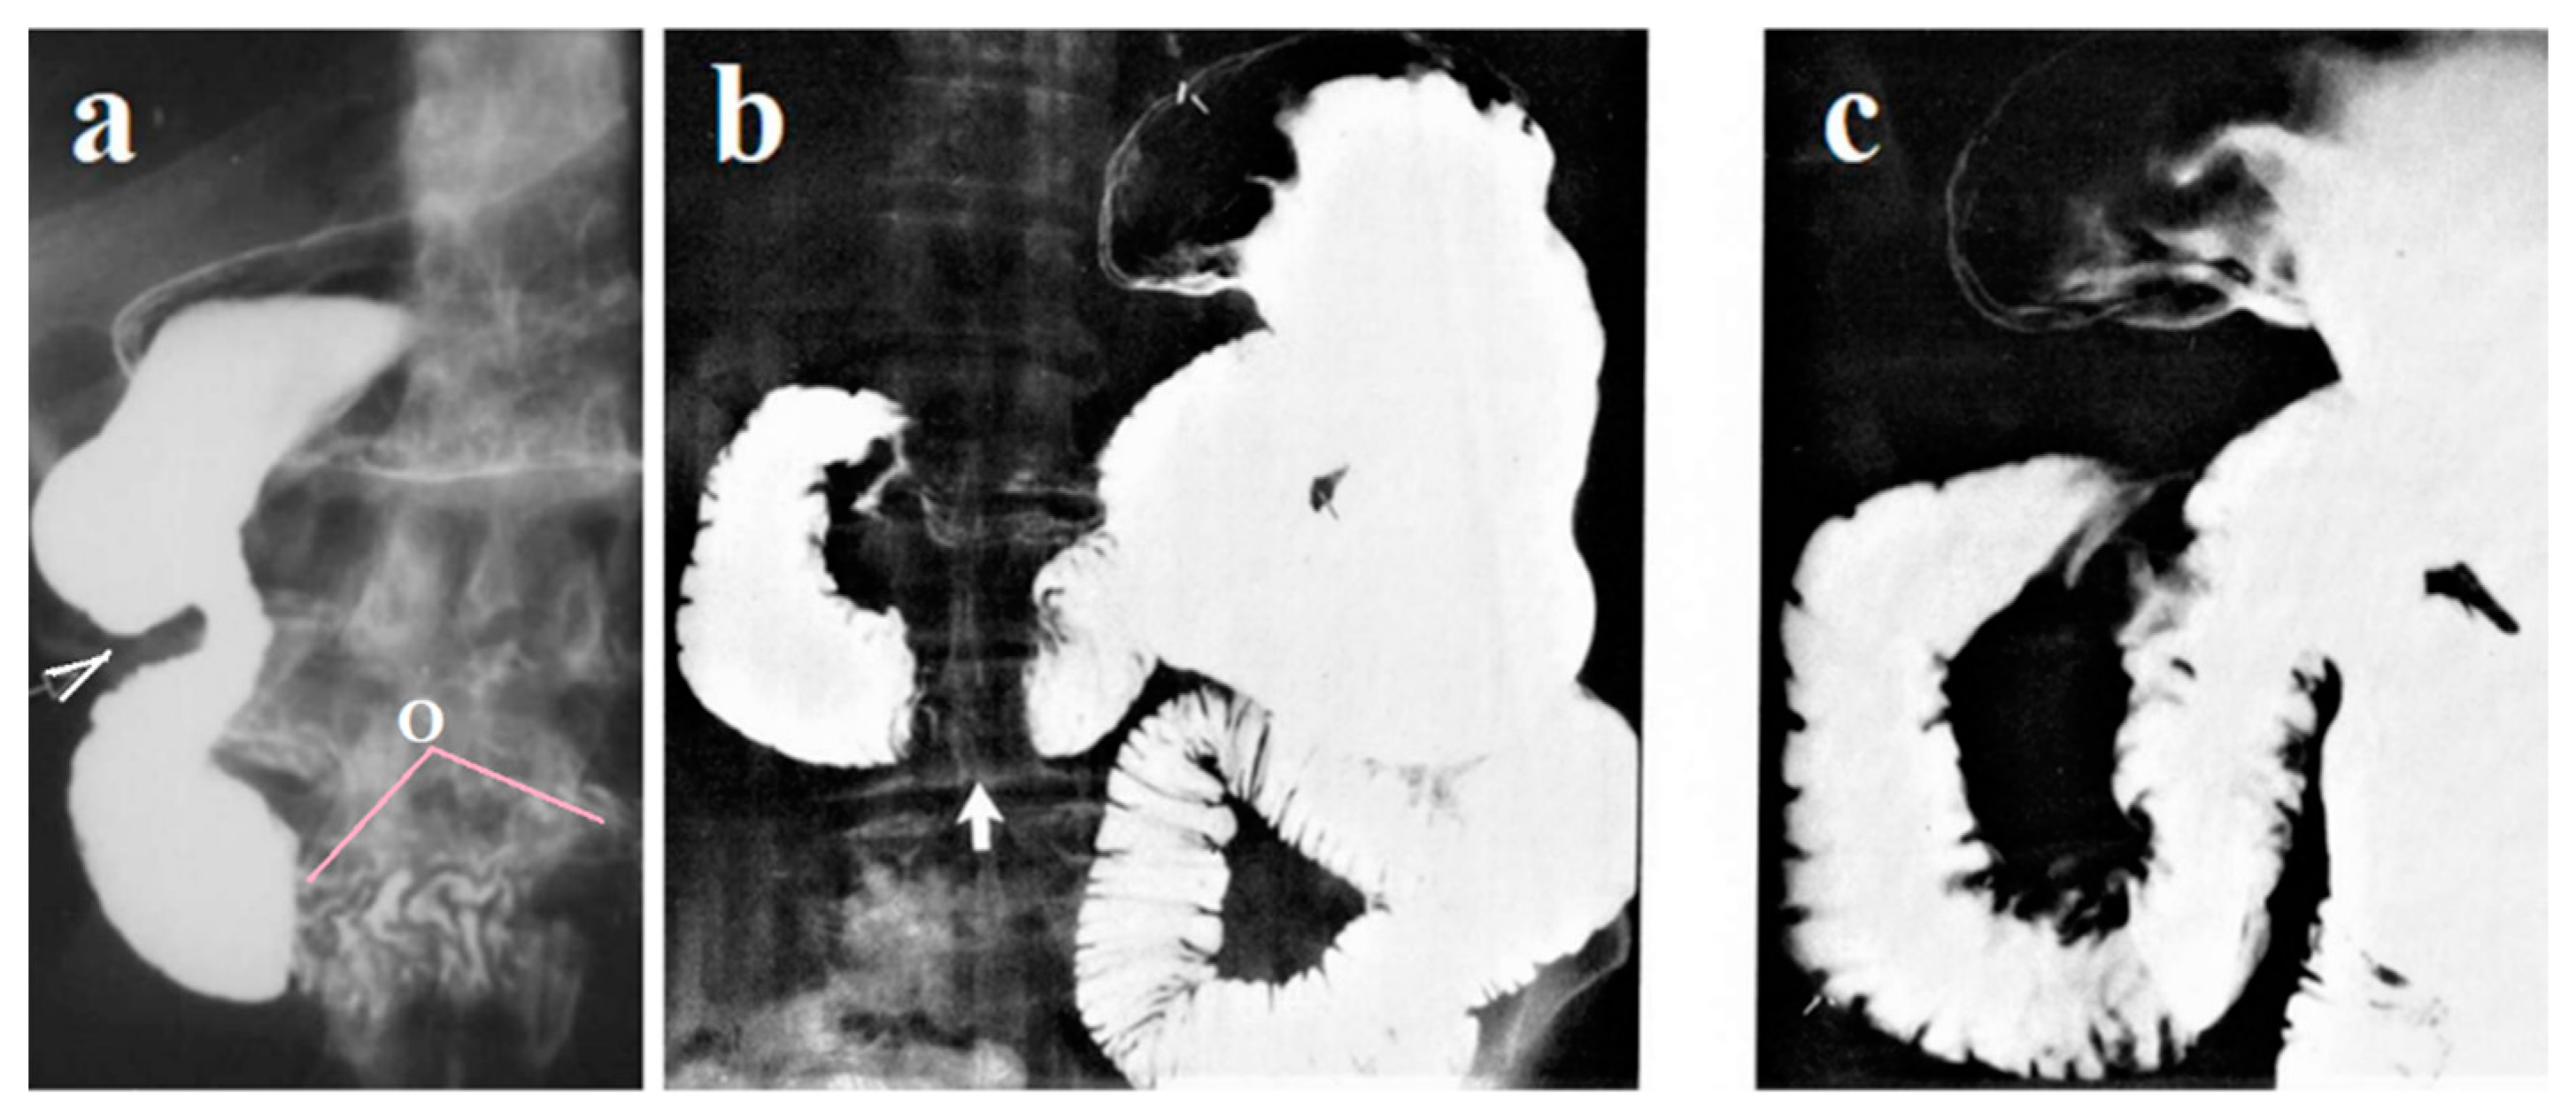

The post bulbar sphincter (PBS), together with the pyloric sphincter (PS), provides evacuation of the chyme from the stomach as portions of a certain volume

(Figure 1A). When the acid bolus reaches the Ochsner’s sphincter, which is in the 3rd part of the duodenum, it causes of its contraction, which prevents entering aggressive chyme to the jejunum

(Figure 1B). As a result of the Ochsner’s sphincter contraction, the bolus is thrown cranially, but Kapanji’s sphincter contraction, it is again thrown to the Ochsner’s sphincter. This pendulum movement of the bolus between the Ochsner and Kapanji sphincters occurs several times. During this time, the chyme mixes with bile and pancreatic juice, which raise the pH of the chyme. When the pH reaches a level that is safe for the jejunum, Ochsner’s sphincter opens, and bolus passes into the jejunum [

1,

3].